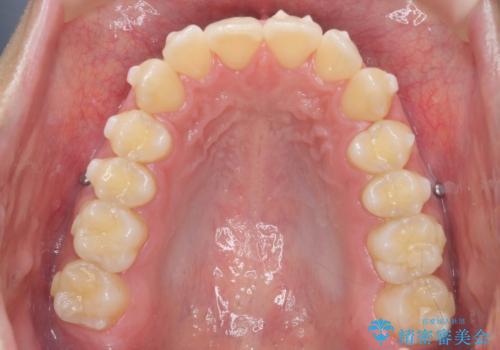

過蓋咬合・上顎前突・叢生を改善するマウスピース矯正

・前歯の深い噛み合わせ (過蓋咬合)

・上顎前突(Angle Class2)

・叢生(がたつき)

以上のような問題点をマウスピース矯正インビザラインとマイクロインプラントを用いて矯正治療を行い改善して行きます。